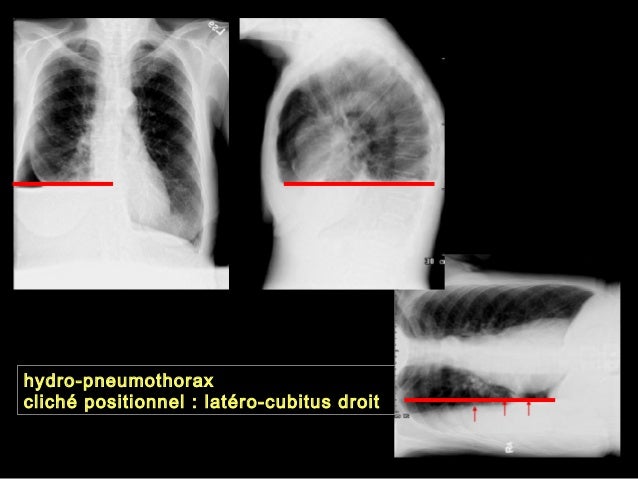

Www Ch Carcassonne Fr Imgfr Files Drainage thoracique powerpoint mr glapiack Pdf